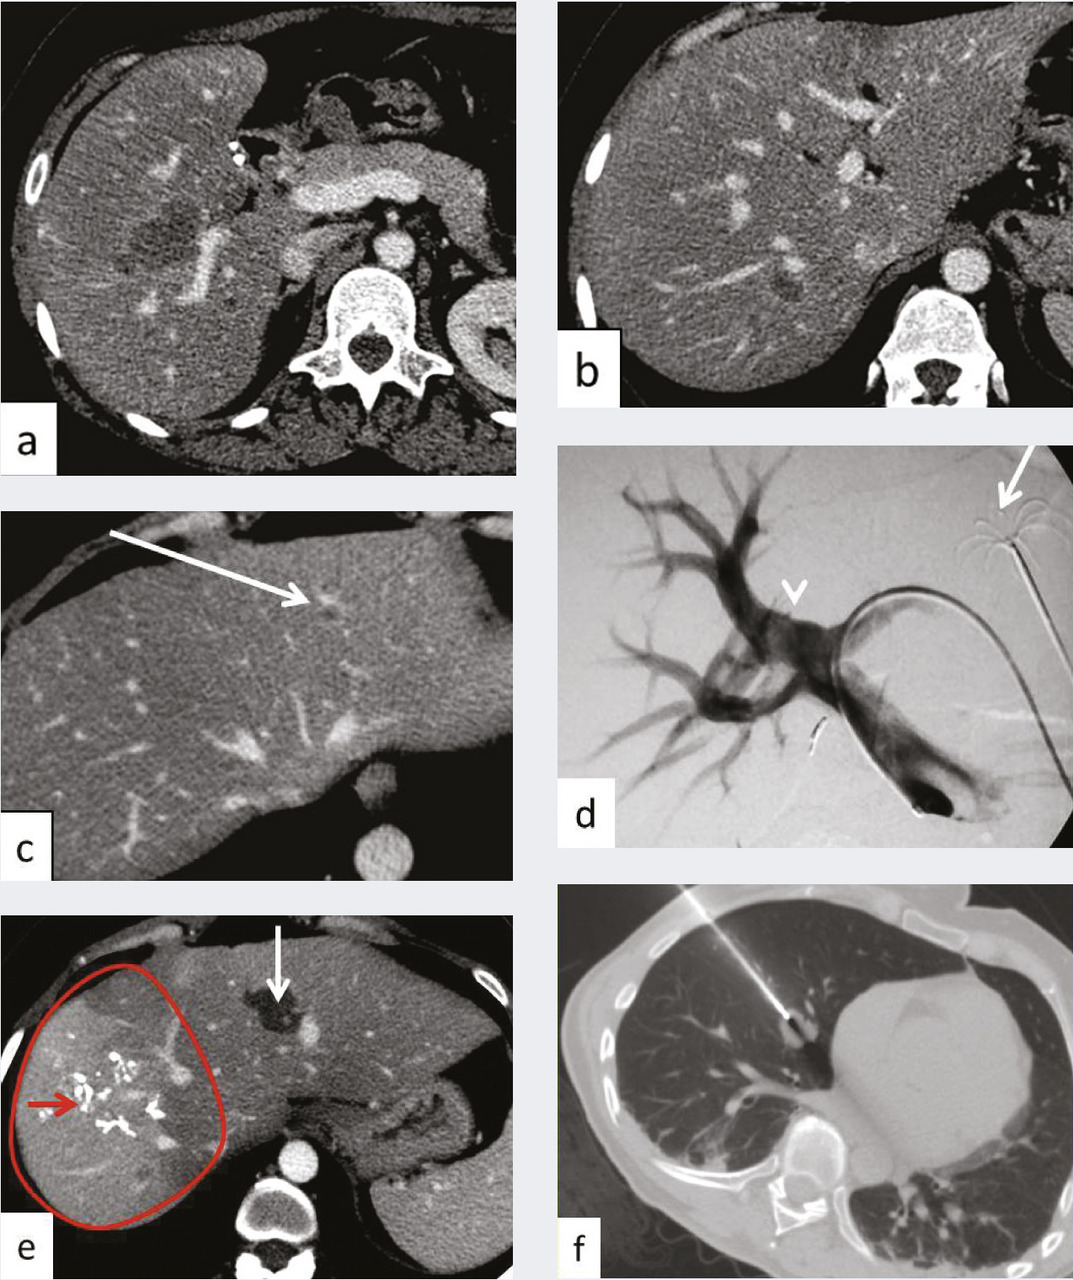

À côté de la voie endovasculaire, une deuxième approche est apparue dans les années 2000 avec l’utilisation d’aiguilles dont l’extrémité est mise en place dans la tumeur par voie percutanée sous contrôle de l’imagerie, le plus souvent l’échographie ou la tomodensitométrie. L’aiguille libère dans la tumeur un courant de radiofréquence qui provoque une augmen- tation locale de la température et la détruit (fig. 6 et 7 ). Ces techniques d’ablathermie constituent un progrès majeur, et d’autres agents physiques tels que les micro-ondes ou la cryogenèse ont été développés par la suite.11, 12 Il est même possible de détruire la tumeur sans effraction cutanée à l’aide d’ultrasons focalisés de haute énergie.13

Les ablations peuvent être thermi- ques par radiofréquences (fig. 6 et 7 ), micro-ondes, laser et cryoablation, on non thermiques par injection d’un agent chimique ou par électroporation.14

Atropho-hypertrophie hépatique par embolisation portale

L’apport sanguin hépatique est issu pour 30 % de l’artère hépatique et pour 70 % du tronc porte. L’occlusion d’une branche portale droite s’accompagne ainsi d’une redistribution sanguine dans la branche gauche avec en corollaire une hypertrophie des segments hépatiques alimentés par la branche perméable du lobe gauche.

Une hépatectomie ne peut être réalisée que s’il reste au moins 30 % de volume hépatique après chirurgie pour éviter une insuffisance hépatocellulaire aiguë postopératoire. Ainsi dans le cas d’un patient qui nécessite une hépatectomie droite en raison de la maladie métastatique et dont le foie gauche est épargné mais a un volume inférieur à 30 %, ce traitement de radiologie inter- ventionnelle guidée par l’imagerie avec embolisation des branches portales droites va permettre d’ob- tenir une hypertrophie hépatique du foie gauche par redistribution vasculaire permettant, dans un délai en général de 40 jours, une intervention chirurgicale. Il est à noter que l’éventuelle présence d’une localisation secondaire dans le foie gauche peut être traitée par thermothérapie dans le même temps que l’embolisation portale (fig. 6 ).

Ce traitement est réalisé sous anes- thésie générale, avec possibilité de prise en charge ambulatoire.